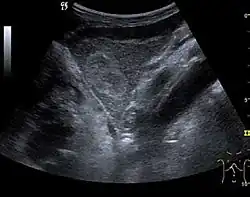

The ultrasound appearance is a well defined lesion, with very thin, almost unapparent walls, without circulatory signal at Doppler or CEUS investigation. The content is transonic suggesting fluid composition. The presence of membranes, abundant sediment or cysts inside is suggestive for parasitic, hydatid nature. Posterior from the lesion the acoustic enhancement phenomenon is seen, which strengthens the suspicion of fluid mass. They typically displace normal liver vessels but no vascular or biliary invasion occurs.

Liver cyst

Hydatid liver cyst. Diagnostic criteria are the presence of membranes and sediment inside.